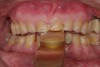

Figure 3  Preoperative view. Note the worn incisal edges and end-on-end occlusal relationship requiring an increase in OVD to restore.

Figure 3